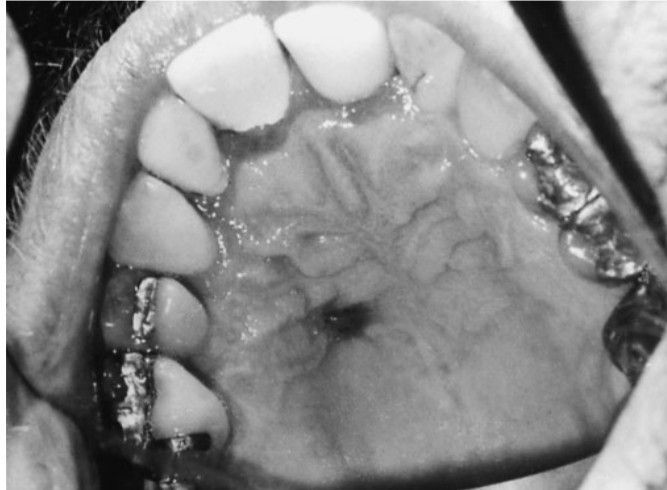

Nevocellular nevus

Nevocellular nevus of the palate. The nevus is raised and gray brown.